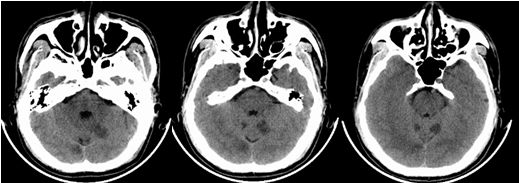

入院时颅脑CT(3.19)小脑梗塞

术后复查颅脑CT